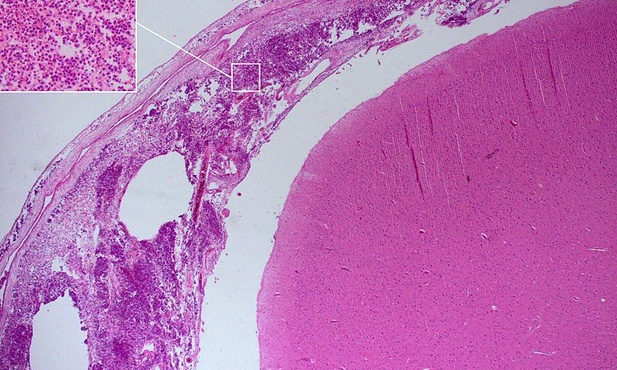

We współpracy z Instytutem Fizyki PAN w Warszawie, IChF PAN opracował specjalne podłoża z tlenku cynku. Podłoża te wykorzystano do pomiarów metodą SERS stężeń pewnego związku - neopteryny w próbkach płynu mózgowordzeniowego. Próbki te - udostępnił je Narodowy Instytut Leków (NIL) w Warszawie - pochodziły od pacjentów z wcześniej zdiagnozowanym zapaleniem opon mózgowych. Okazało się, że w płynie mózgowym takich osób stężenie neopteryny było dziesięciokrotnie wyższe niż w próbce referencyjnej, pobranej od zdrowej osoby.

"Podwyższone stężenie neopteryny to cenna informacja, że organizm walczy z chorobą o podłożu bakteryjnym. Jednak zapalenie opon mózgowych może być efektem zakażenia różnymi gatunkami bakterii. Żeby działać naprawdę efektywnie, lekarz powinien wiedzieć, z którym gatunkiem ma właśnie do czynienia" - podkreśla dr hab. Anna Skoczyńska, prof. NIL.

Pomiary widm ramanowskich bakterii w płynie mózgowo-rdzeniowym okazały się trudne: w przeciwieństwie do cząsteczek chemicznych, które nie przemieszczają się po podłożu, bakterie znajdują się w ciągłym ruchu. Przed naukowcami pojawiło się wyzwanie: należało opracować podłoża, które nie tylko zapewnią wzmocnienie sygnału ramanowskiego, ale także odfiltrują bakterie z płynu oraz skutecznie je unieruchomią na czas pomiaru.